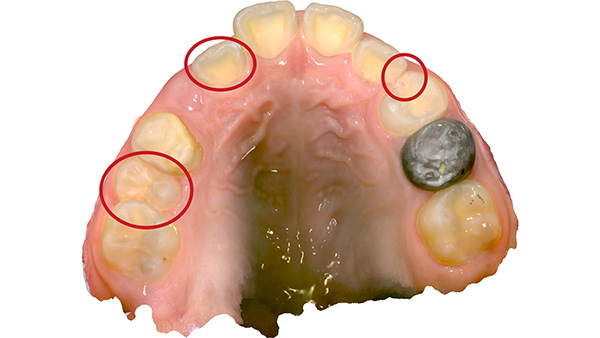

A patient had crowding in the upper canine area, a crossbite on one side, and a second premolar that was trapped and unable to erupt. Instead of waiting until adulthood (which might have required extraction-based orthodontics), we used a special removable appliance called a Sagittal Appliance to gently move the front teeth forward and molars backward, creating room for proper eruption.

This appliance includes push springs to move the incisors forward and distal screws to expand the space for the premolars—one of the most complex and precise devices to make!